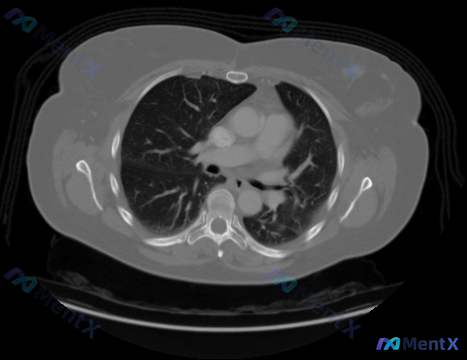

今天看到一个提问,直接给了一张胸部CT纵隔窗的横断面,问「图片中显示的癌症的类型和分期是什么」。 看完片子第一反应:这个问题的预设前提可能不成立。先整理一下影像里的核心信息: 先列一下这张CT的「阳性」和「阴性」发现 明确阴性(无恶性征象): - 纵隔(气管隆突下、支气管周围、主肺动脉窗)未见异常肿...